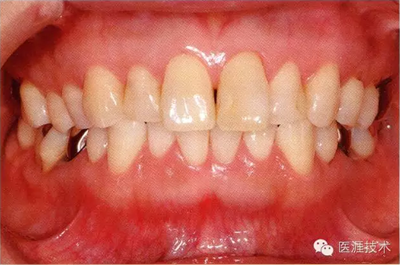

22歲男性牙齦炎的臨床圖像

22歲男性,抽煙(1天約15根,煙齡5年)。刷牙狀態(tài)不佳。抽煙者特有的纖維性牙齦,未見發(fā)紅、腫脹。探針觸診,所有部位均出血。X線牙片未見骨吸收,診斷為牙齦炎。